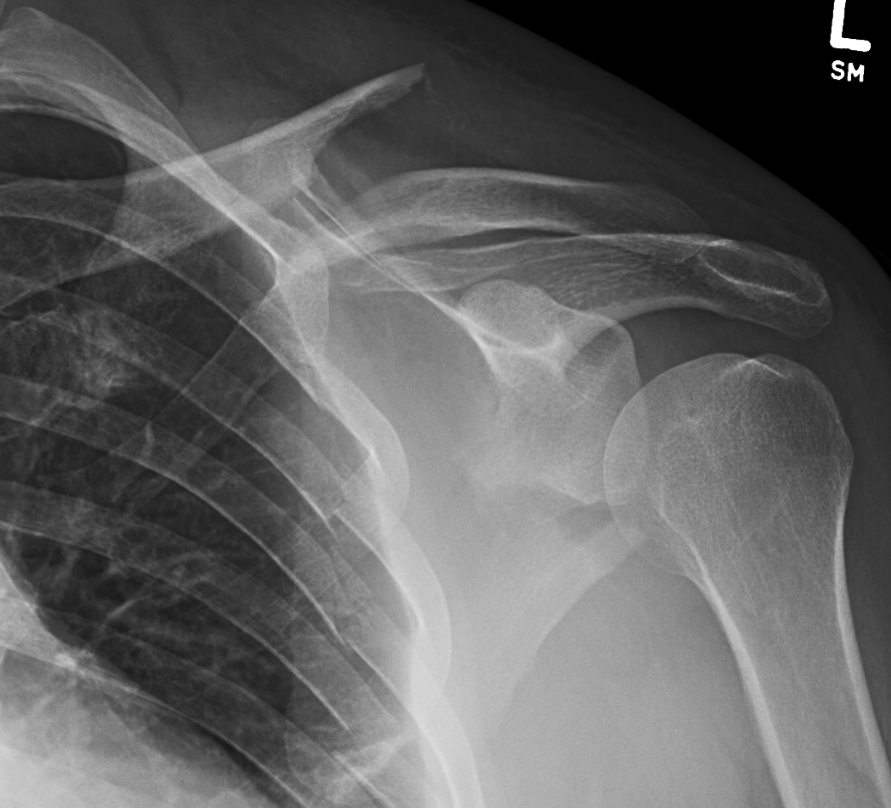

Glenoid fracture + lateral clavicle fracture + acromial fracture